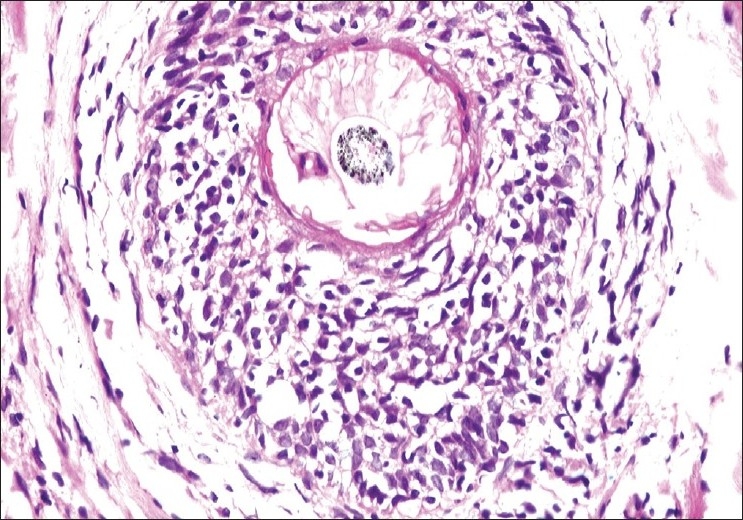

The histological features are depicted in Table 1. The most striking feature on biopsy, discernible even on scanning magnification, was a moderate-to-dense folliculotropic cellular infiltrate [Figure 2]. This infiltrate was populated by monomorphous lymphocytes in two cases, while the other two showed an admixture of many eosinophils (> 20 per section). There was invasion of the follicular units by these lymphocytes, with tagging along the basal layer in rows [Figure 3]. The infiltrate was seen involving the bulb of the follicle in all four cases, in addition to the isthmus in two cases. The lymphocytes showed enlargement and convoluted nuclei, surrounded by haloes. The case that showed a profusion of eosinophils also showed epithelioid granulomas centered on the involved follicles. [Figure 4] Special stains for fungi and Mycobacteria were negative. Mucin was present within the follicle in all four cases, which was highlighted by an Alcian blue stain [Figure 5].

| Figure 2 Dense folliculotropic, monomorphous lymphocytic infiltrates (H and E, × 200)